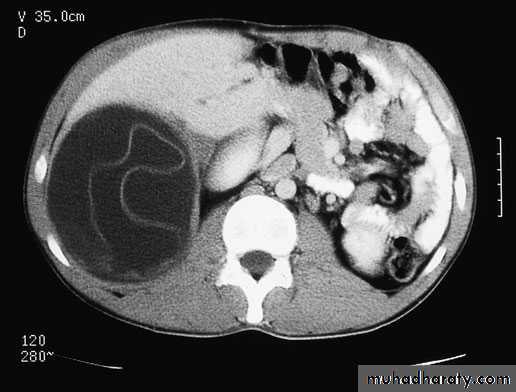

Hydatid Liver CystEchinococcosis (hydatid disease) is a zoonosis caused by the larval stage of Echinococcus granulosus . Humans are accidental intermediate hosts, whereas animals can be both intermediate hosts and definitive hosts. The two main types of hydatid disease are caused by E. granulosus and E. multilocularis. The former is commonly seen in the Mediterranean, South America, the Middle East, and is the most common type of hydatid disease in humans.In humans, 50–75% of the cysts occur in the liver, 25% are located in the lungs, and 5–10% distribute along the arterial system.

PathologyThe typical hydatid cyst has a three-layer wall surrounding a fluid cavity. The outer layer is the pericyst, a thin, indistinct fibrous tissue layer representing an adventitial reaction to the parasitic infection. The pericyst acts as a mechanical support for the hydatid cyst . As the cyst grows, bile ducts and blood vessels stretch and become incorporated within this structure, which explains the biliary and hemorrhagic complications of cyst growth . Over time, the pericyst calcifies. The intermediate layer of the cyst itself is the ectocyst or laminated membrane and is bluish-white, gelatinous.The inner layer or endocyst is the germinal membrane, responsible for the production of clear hydatid fluid, the ectocyst, scoleces, and daughter cysts. The endocyst is 10–25 m thick and attached tenuously to the laminated membrane. The function of the inner layer is important for the nutrition of the cyst. The inner layer also has a proliferative function producing the ectocyst and scoleces(daughter cyst). In uncomplicated cysts, the cyst cavity is filled with sterile, colorless, antigenic fluid containing salt, enzymes, proteins, and toxic substances.

Serological test e.g’ The Casoni test are no longer used due to their low sensitivities. Determination of specific antigens and immune complexes of the cyst with enzyme-linked immunosorbent assay (ELISA) give a positive result in more than 90% of patients. The arc 5 antibody test involves precipitation during immunoelectrophoresis of the blood of patients with the antigen. Positivity for this test is 90%.RadiologyChest radiographs may show an elevated diaphragm and concentric calcifications in the cyst wall, but are of limited value. Ultrasound and CT are considered the first choice for imaging . Classic findings of hydatid cysts are calcified thick walls, often with daughter cysts. Ultrasound defines the internal structure, number, and location of the cysts and the presence of complications.

Computed tomography gives similar information to ultrasound, but more specific information about the location and depth of the cyst within the liver. Daughter cysts , and the volume of the cyst can be estimated. CT is imperative for operative management, especially when a laparoscopic approach is utilized.MRI provides structural details of the hydatid cyst, but adds little more than ultrasound or CT, and is more expensive. Endoscopic retrograde cholangiopancreatography (ERCP) may show communication between the cysts and bile ducts and can be used to drain the biliary tree before surgery.